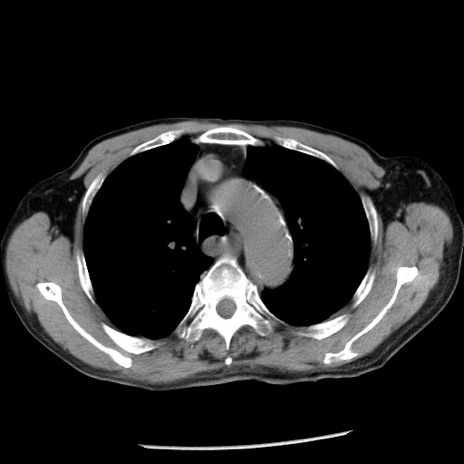

症例26(横断像)

冠状断像

【症例】80歳代男性

【主訴】嘔吐

【現病歴】昨晩2回嘔吐あり、今朝になっても嘔吐あり。来院。

【既往歴】胃潰瘍

【身体所見】意識清明、BT 37.6℃、BP 166/95mmHg、HR 100bpm、SpO2 97%、腹部:平坦・軟、腸蠕動音聴取良好、圧痛なし。

【データ】WBC 21900、CRP 1.46